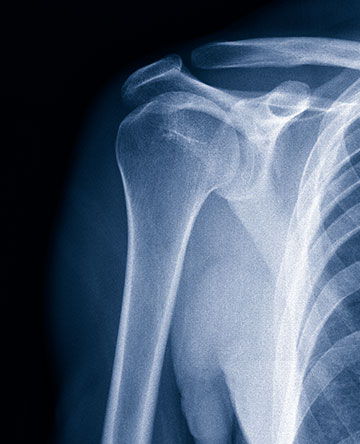

The shoulder specialist treats a wide variety of shoulder problems both with and without surgery. These problems may arise from overuse, aging or injury and are commonly seen in workers, recreational athletes and everyday patients of any age. Common injuries include fractures, separations, dislocations labral tears and rotator cuff tears. Common surgical procedures include rotator cuff surgery, labral repair and shoulder replacement. Several of our physicians have an expertise in arthroscopic shoulder surgery, a minimally invasive way to treat certain shoulder problems, and shoulder replacement surgery.